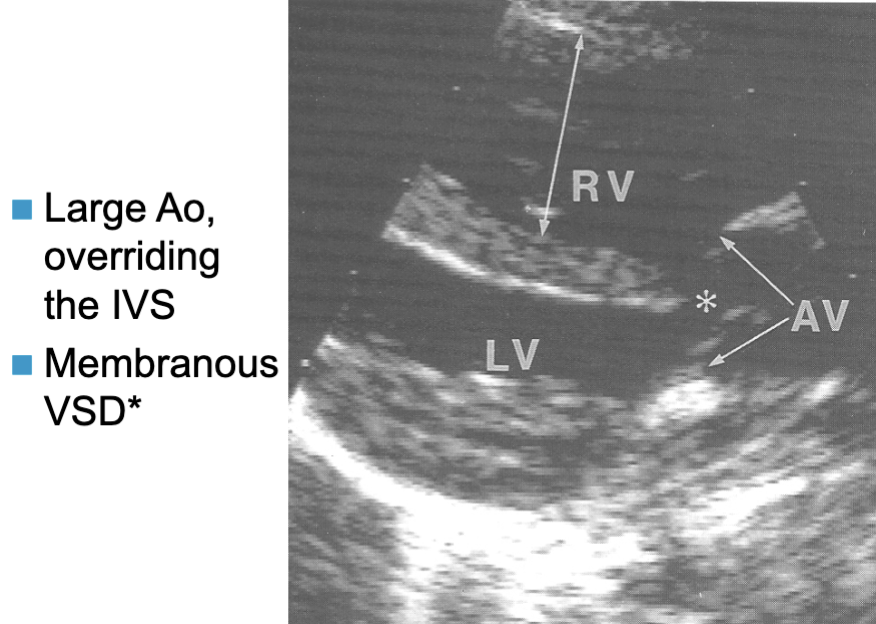

Tetralogy of Fallot (TOF)

Combination of 4 congenital lesions:

membranous VSD

anterior + rt displacement

overriding Ao (over the IVS)

may be infundibular / subinfundibular stenosis

usually d/t posterior malalignment of IVS from overriding Ao

PV or PA may be atretic

RVOTO / PS

RVH

Tetralogy of Fallot key findings:

TOF 2D findings:

PLAX

overriding Ao

VSD